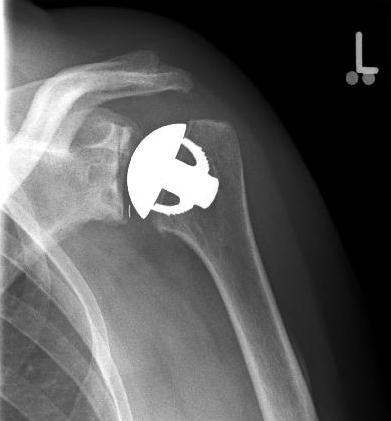

Abbildung2Abbildung1

left: X-ray image of an omarthrosis

right: X-ray of a healthy shoulder joint